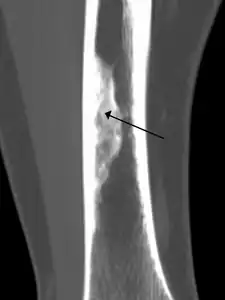

X-ray of nonossifying fibroma of distal tibia.

Diagnosis is by X-ray or MRI, usually when investigating a person for something else.[3] Medical imaging typically shows a well marginated radiolucent lesion, with a distinct multilocular appearance, sometimes looking like bubbles.[3] It is usually around 1-2cm in size, but be as large as 7cm.[4] They consist of foci consist of collagen rich connective tissue, fibroblasts, histiocytes and osteoclasts.[3] Usually no treatment is required.[4] Surgical curettage and bone grafting may be required if it is large.[4]

It is usually iagnosed by x-ray or MRI, when investigating another problem.[1] The tumor presents as a well defined radiolucent lesion, with a distinct multilocular appearance, sometimes looking like a "soap bubble".[2] If small and no symptoms, then biopsy is not needed.[1]